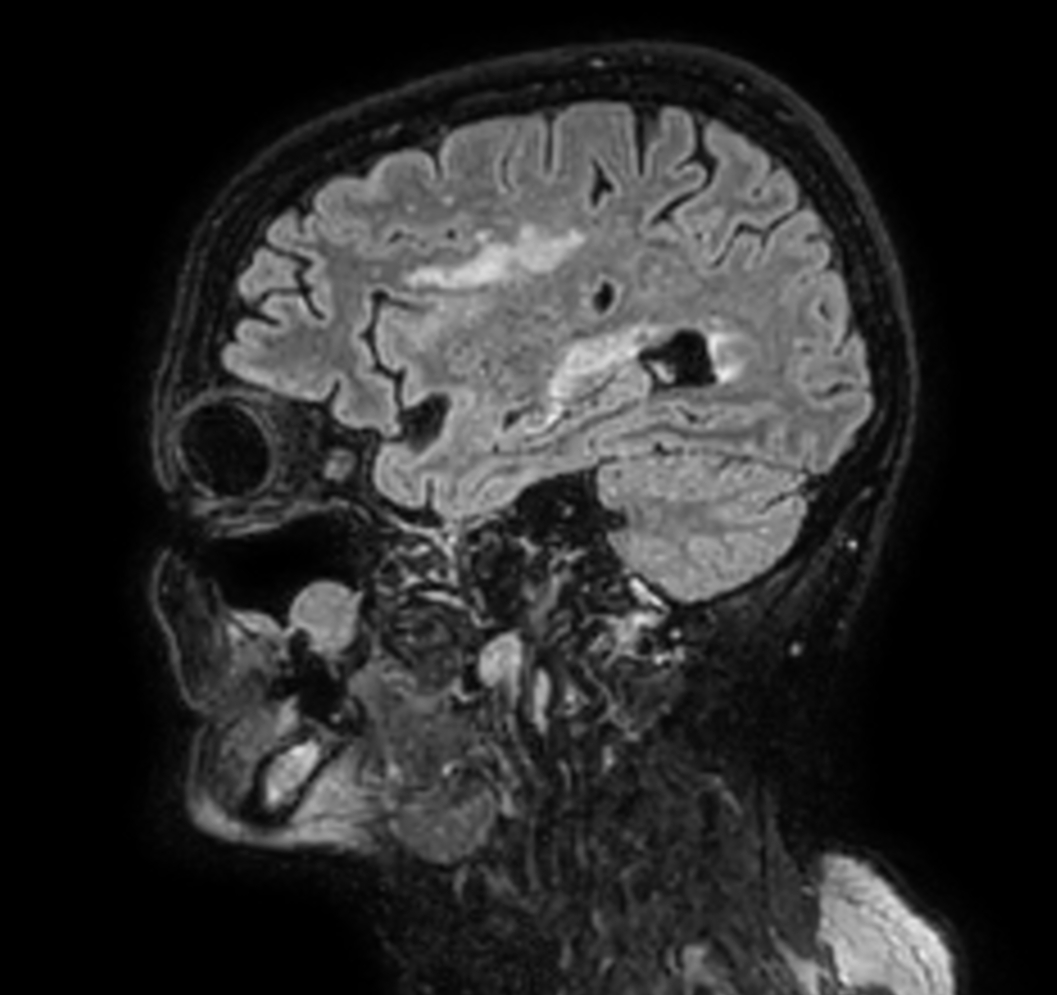

Sagittal 3D VIEW - T2w FLAIR